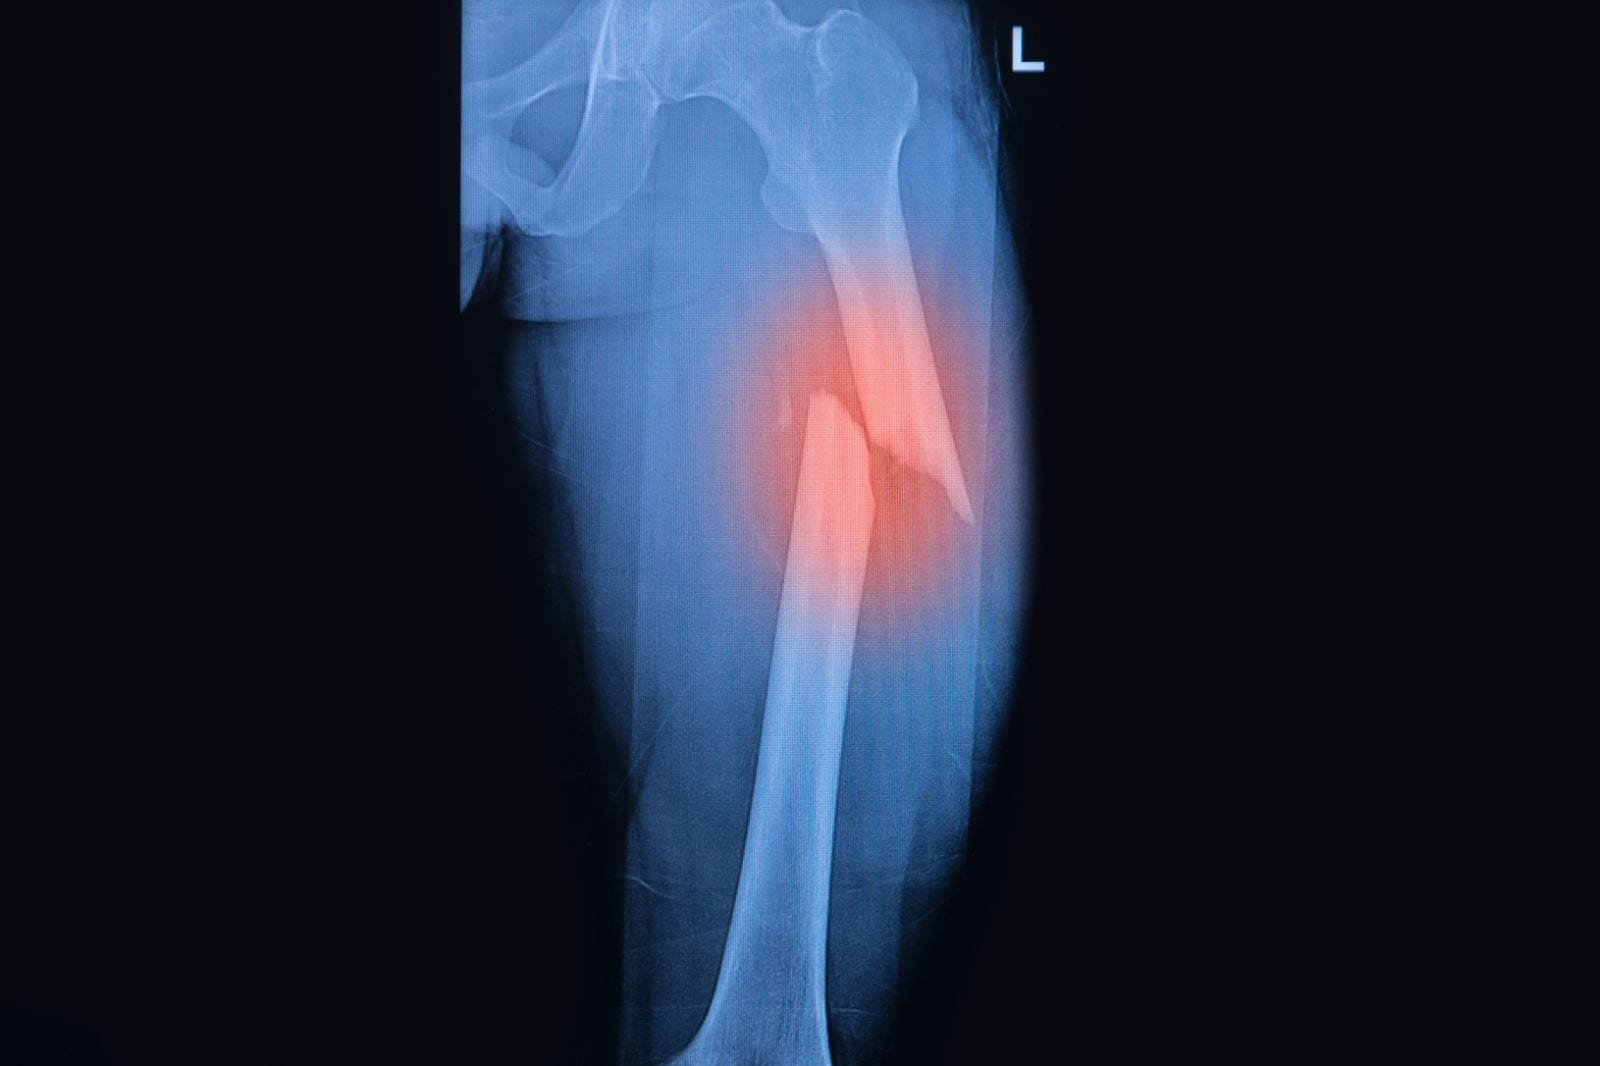

- Las fracturas abiertas o expuestas son las que el hueso quebrado sobresale de la piel, generado una herida.

- En cambio las fracturas cerradas es cuando ocurre una rotura pero el hueso no sobresale de la piel.

Dependiendo de la clase de fractura es que variará el tiempo de recuperación, así como el tratamiento de la lesión. Si bien no en todos los casos será necesaria la intervención quirúrgica, en la gran mayoría de estos se necesita alguna férula o yeso para inmovilizar el hueso durante su recuperación.

- Evita mover a la persona en caso de que la lesión haya ocurrido en la cadera, los muslos o la pelvis. Solo se deberá hacer en caso que sea totalmente necesario para ello solo tendrás que moverla a un lugar seguro, deberás tomarla de la ropa arrastrarla